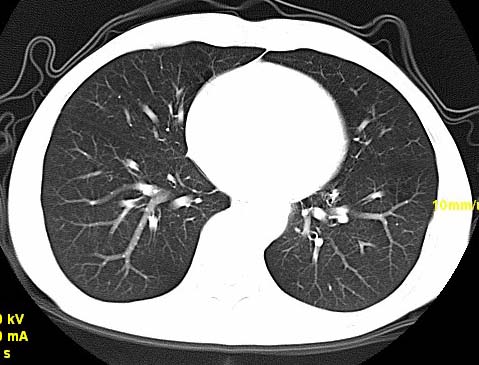

以下是引用wangzhengyuan在2007-11-11 23:31:00的发言:[br]钙化灶,看上去不像转移。

以下是引用zjzjr在2007-11-12 8:35:00的发言:[br]考虑错构瘤,建议定期复查.

以下是引用卜一在2007-11-12 5:59:00的发言:[br]病灶本身不像转移,不知有没有以前的胸部ct片,若有,则可以对比以下,若是新出现病灶,应高度警惕“转移”的可能![br]